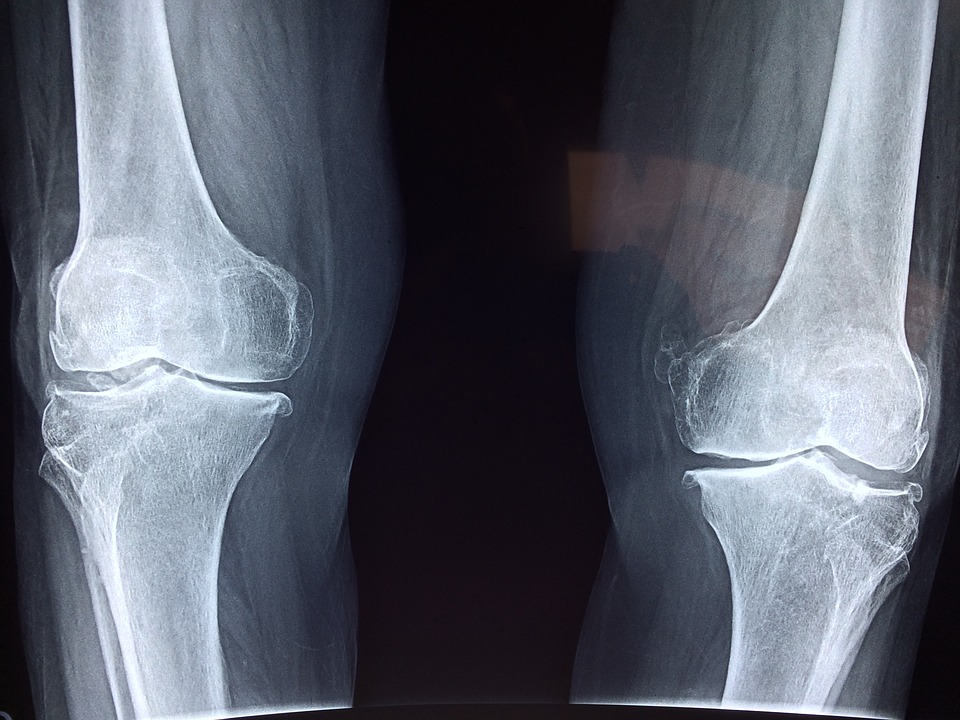

Galleria foto - Osteofitosi: di cosa si tratta? Cause, sintomi e cura Foto 1